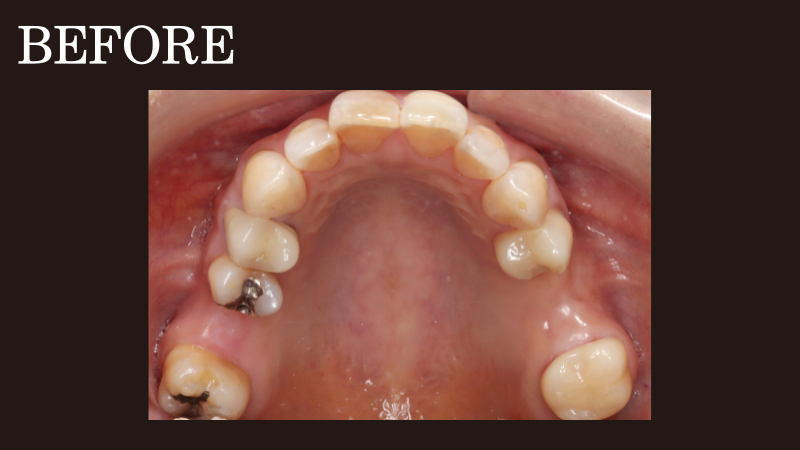

部分入れ歯の症例(10)

ノンクラスプデンチャー

(コンティース)

case10

違和感がなく、しゃべりやすい入れ歯がほしい

50代女性

お口に入れている時の違和感がなく、会話の邪魔にならない入れ歯を希望されて部分入れ歯を作り直した患者さまです。

ご要望を叶えるため、抜歯後に目立たない部分入れ歯「エステショット(ノンクラスプデンチャー)」をお作りしたところ、自然な見た目で入れ歯と気づかれない点やしっかり噛める点は大変ご満足いただきましたが、会話する際の違和感が気になるとお悩みのご様子でした。

そこで新たにご提案したのが、2024年11月に登場した最新の入れ歯「コンティース(ノンクラスプデンチャー)」への作り替えです。

コンティ―スとは、3Dレーザープリンターによるチタン加工技術を用いて開発された新しい入れ歯のこと。

金属が目立ちにくい入れ歯

入れ歯には金属が一部使用されていますが、目立たない位置にあり、入れ歯であることが周囲の人に気づかれにくい設計です。また、この金属部分が滑らかに加工されており、同じノンクラスプデンチャーや他の入れ歯に比べて装着時の違和感が少なくなるよう仕上げられます。

出来上がった入れ歯を患者さまに装着いただいたところ、「入れ歯特有の違和感がなく付け心地がいい」「以前の入れ歯とは比べ物にならないほど話しやすい」と大変喜んでいただけました。

さらに自分の歯で噛んでいた時とほとんど変わらないほど咀嚼力が回復し、しっかり噛めるようになったとの嬉しいお声も。

このように、コンティ―スは発音や会話の邪魔にならない入れ歯です。加えてお口を開けても入れ歯と気づかれにくいため、周囲の目線を気にせず思いきり笑ったり、会話を楽しんだりできます。

コンティース(ノンクラスプデンチャー)で治療。

右上:220,000円

左上:220,000円

計:440,000円(税込)

治療期間・回数

3週間・2回